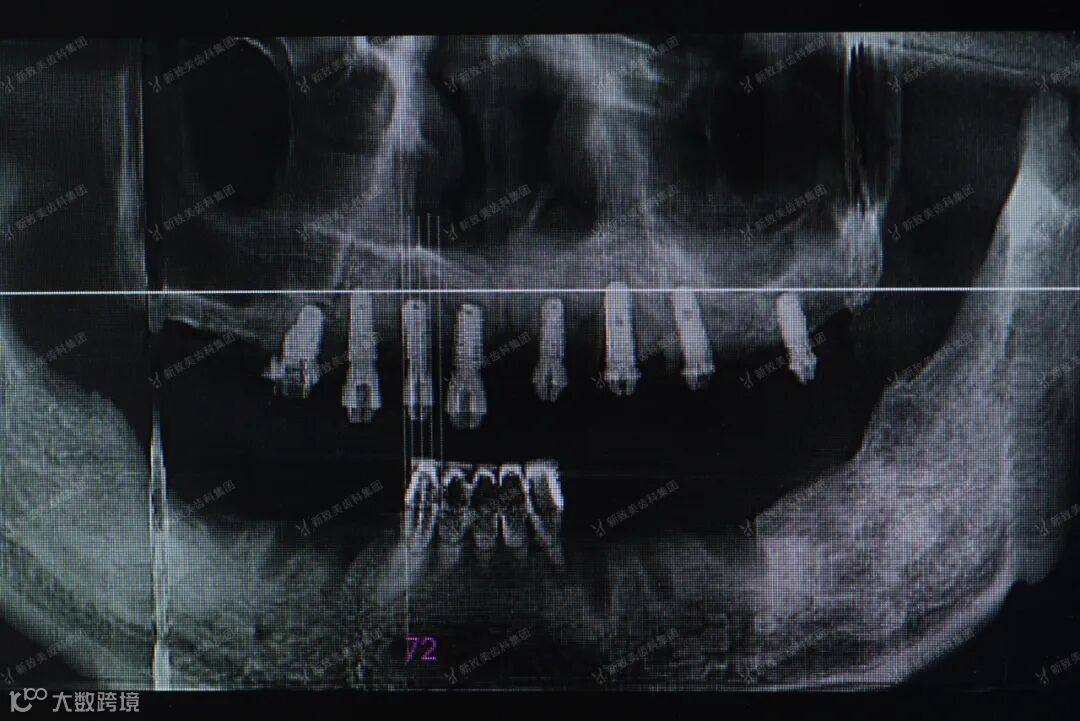

临床种植手术过程